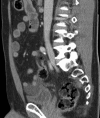

Coronal (1) and saggital (2) reconstructions of the CT scan on admission showing free fluid in the pelvis superior to the bladder and around the liver.